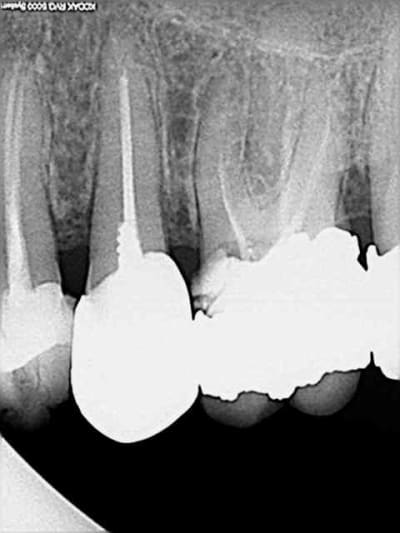

premier retraitement ce jour avec les protaper universal.

la prise en main est facile. On n'est pas dépaysé par rapport aux protaper classiques.

obturation par compactage avec les cones protaper.